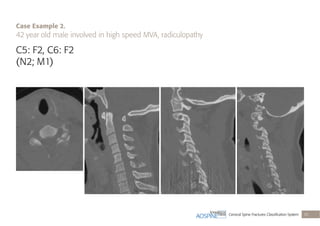

C5: F2, C6: F2

(N2; M1)

C5 and C6 displaced facet fractures (F2),

radiculopathy (N2), posterior capsuloligamentous

complex injury without complete disruption (M1)

Case Example 2.

42 year old male involved in high speed MVA, radiculopathy